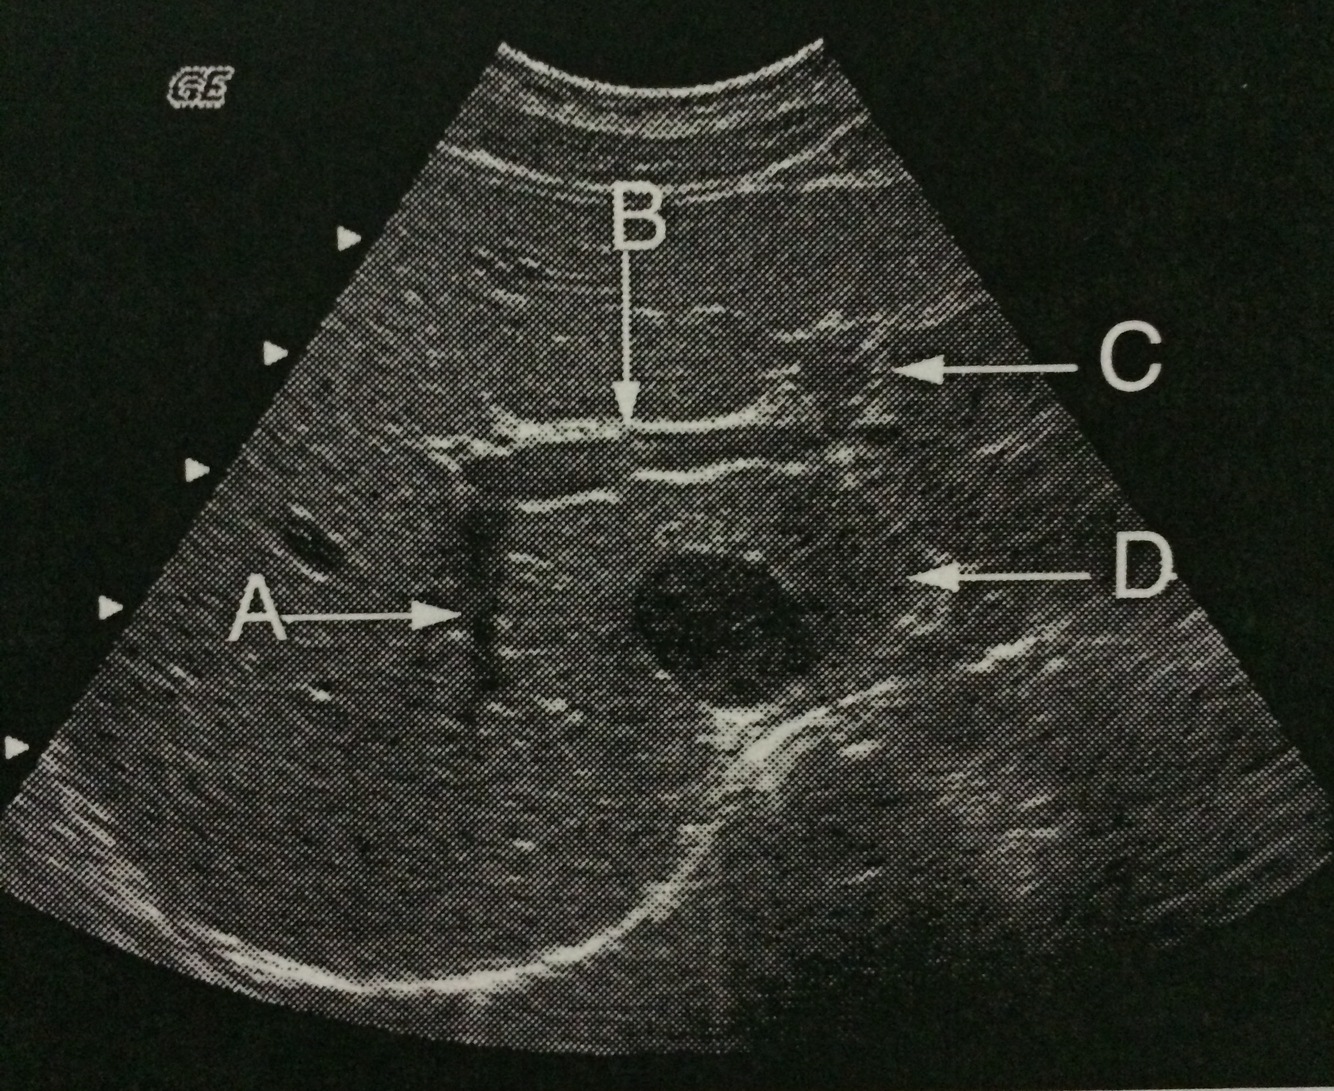

Identify the anatomy labeled A.

Right posterior portal vein branch

Vessel A is located in what lobe of the liver?

Posterior segment right lobe

Identify the anatomy labeled C.

Left portal vein

The arrow labeled D is pointing to what lobe of the liver?

Caudate lobe